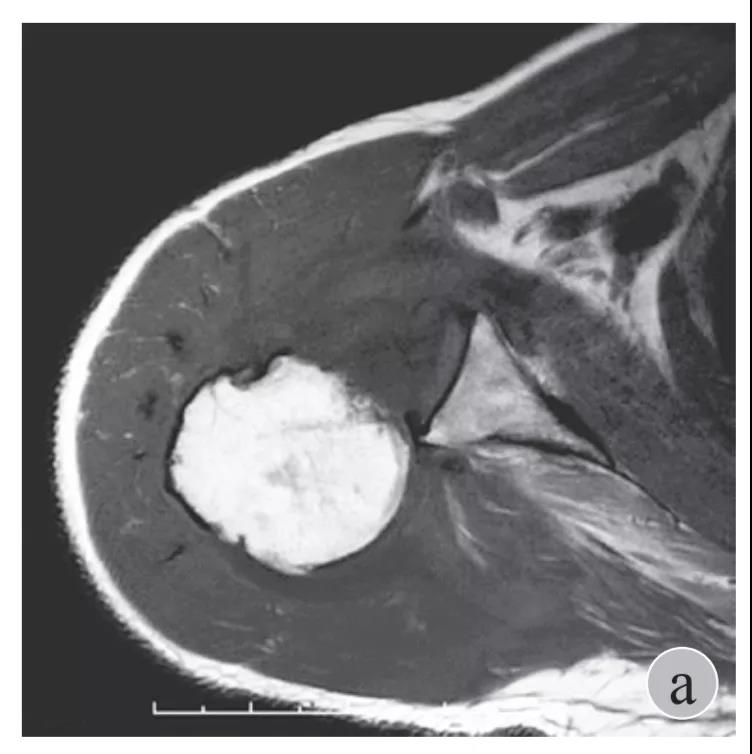

磁共振检查也完善了,还是报了个肩关节半脱位……影像科已经把坑挖好了……

就诊我院后完善CT,诊断明确——左肩关节后脱位: